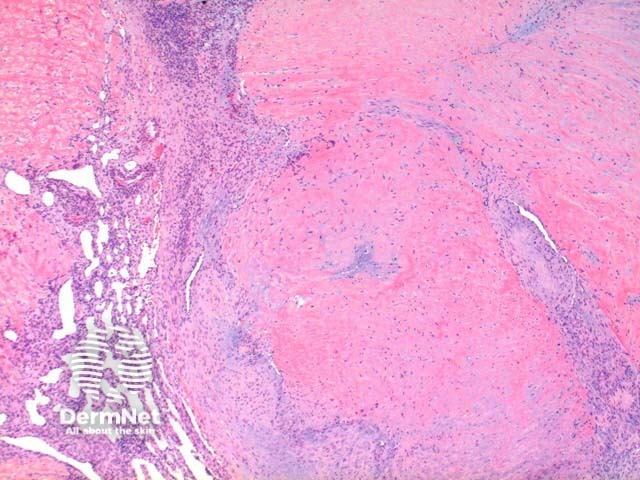

Low power view of myofibroma demonstrates a well defined multinodular tumour arising in the deep dermis or subcutis (Figure 1). Also at low power a branching ‘staghorn’ like pattern of blood vessels can be seen between the tumour nodules (Figure 2). Areas of calcification can often be seen (Figures 2, 3 and 5). The tumour nodules are comprised of a spindle cell proliferation with short plump nuclei (Figures 4,5 and 6). A basophilic tinge in the spindled peripheral component of the nodules is evident (Figures 7 and 8). Sclerotic collagen in the centre of the tumour nodules gives a biphasic appearance to the tumour (Figure 9).